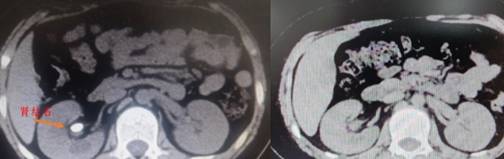

超微通道、完全无管化 湘雅专家为患儿清除肾脏结石推荐人:丁丁小编 发布时间:2023-04-26 11:29:58